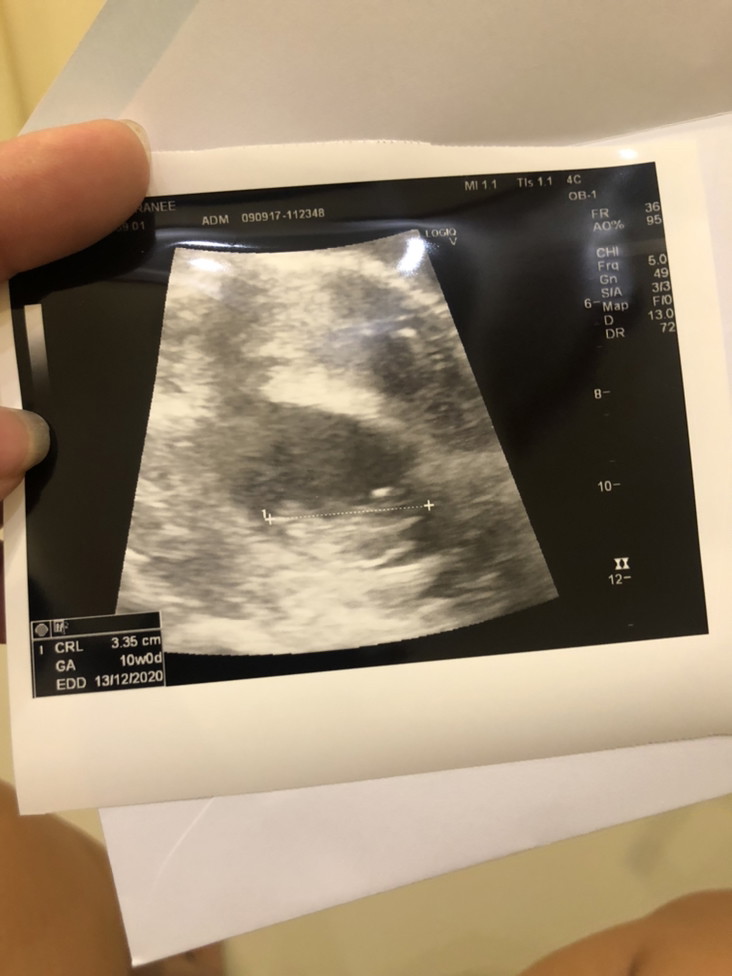

13 /12/63 ค่ะ

10wค่ะ

13/12/20